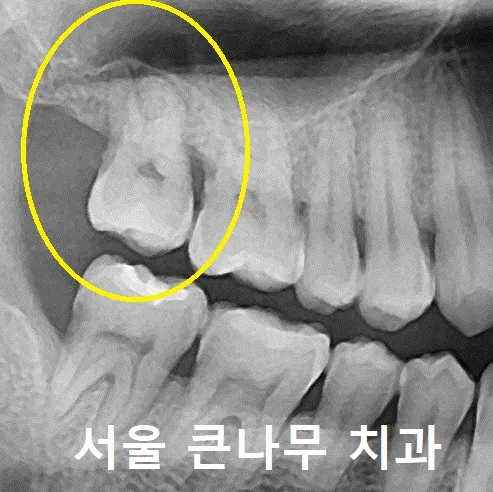

서울큰나무치과에 방문해 주신 40대 남성 환자분입니다.

오른쪽 위 치아가 아파 내원하셨으며, 상태가 좋지 않아 잇몸치료 끝에 발치를 진행하였습니다.

발치 후 사진입니다.

치조골이 부족하여 치조정접근법(crestal approach)로 상악동 골이식술을 진행하였습니다.

수술 전 CBCT 방사선 사진을 찍어 뼈의 양을 더 자세히 살펴보았습니다.